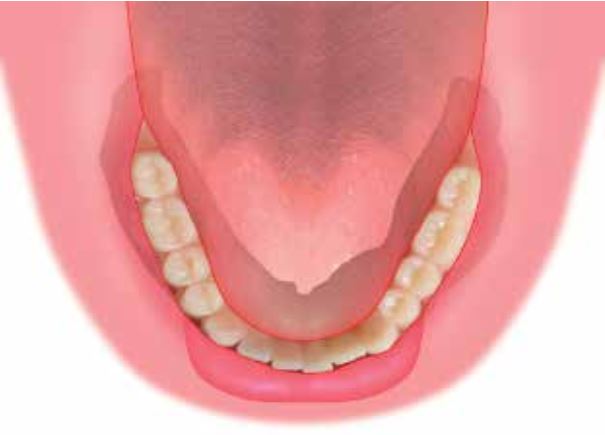

Làm thế nào để đạt được hít dính hiệu quả ở hàm dưới? Câu trả lời là: thông qua một viền hàm liên tục và hoàn toàn kín.

Nói cách khác, không được có bất kỳ điểm nào dọc theo viền hàm cho phép không khí lọt vào và phá vỡ lực hút chân không.

Nếu không có một viền hàm khít hoàn toàn, hàm giả sẽ mất tiếp xúc với mô nền.

Để hàm giả có thể giữ vững vị trí một cách tự nhiên, cần đảm bảo viền hàm giả khít sát liền mạch với niêm mạc phía môi và má, cũng như mô mềm dưới lưỡi.